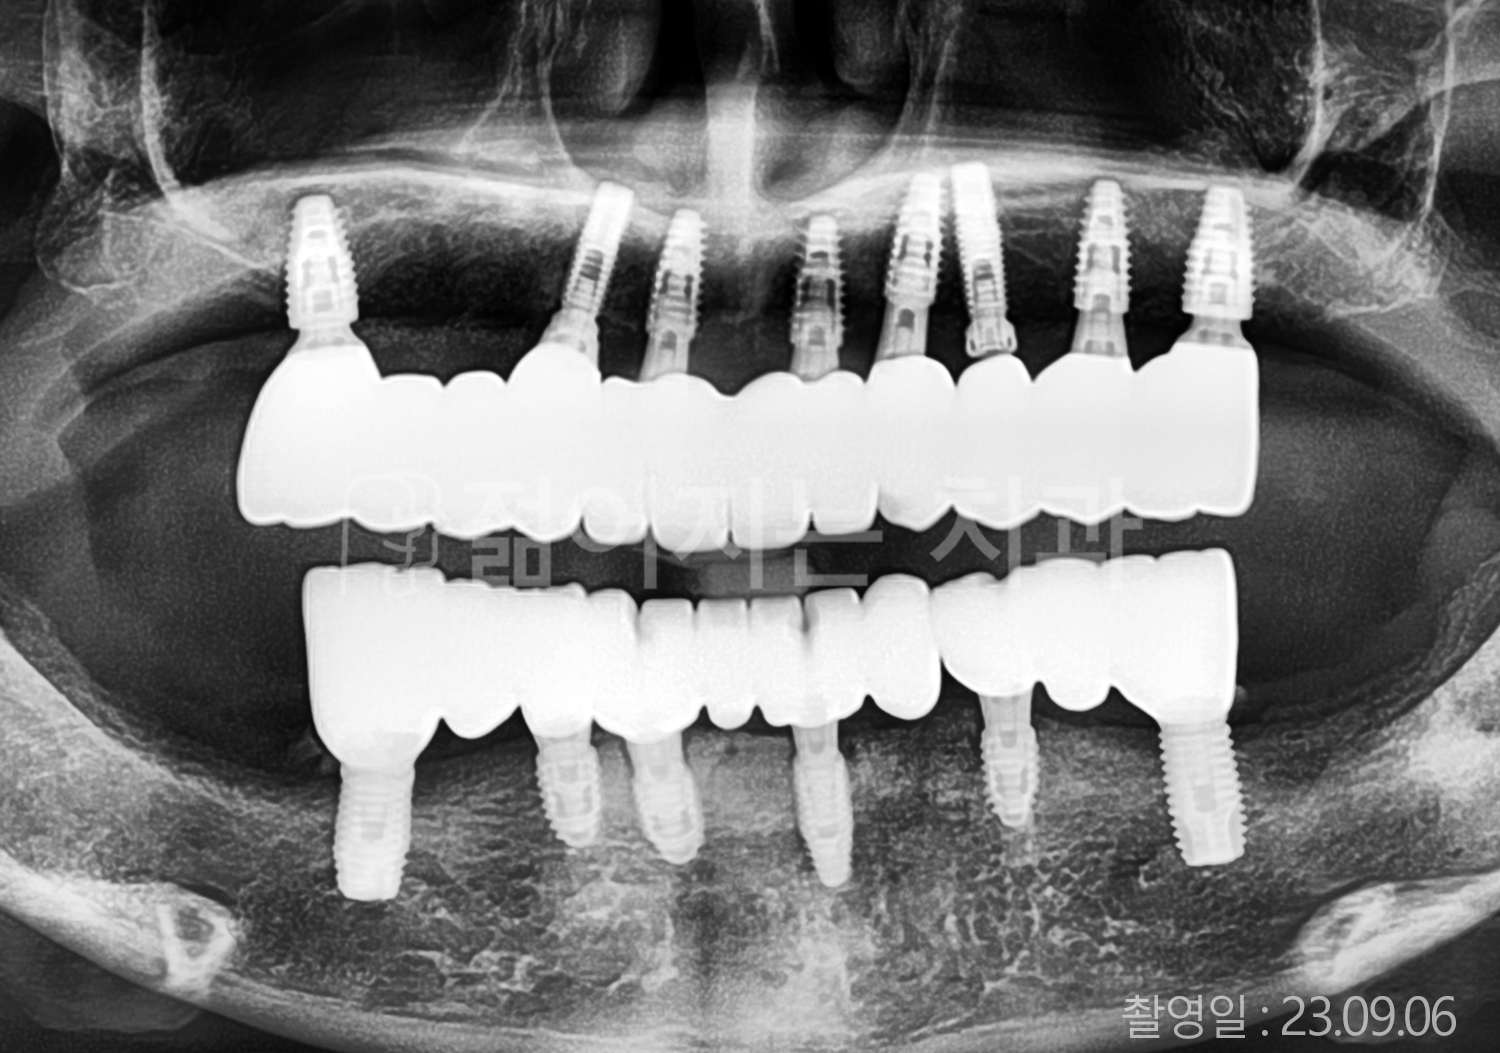

• 60대 고혈압, 고지혈증 전체치아 10개 이상 임플란트

• 70대 전체치아 10개 이상 임플란트

• 60대 전체치아 10개 이상 임플란트

• 50대 전체치아 10개 이상 임플란트

• 50대 고혈압, 고지혈증 전체치아 10개 이상 임플란트

• 60대 고혈압, 당뇨, 고지혈증 전체치아 10개 이상 임플란트

• 80대 고혈압, 당뇨, 골다공증 전체치아 10개 이상 임플란트

• 60대 고혈압 전체치아 10개 이상 임플란트

• 60대 고지혈증 전체치아 10개 이상 임플란트

• 60대 당뇨 전체치아 10개 이상 임플란트